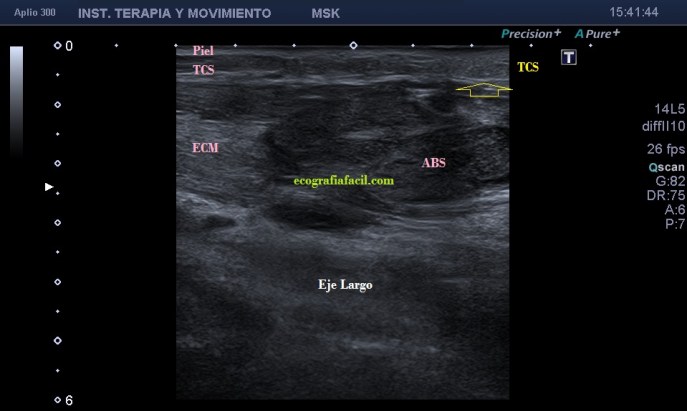

La ecografía muscular realizada evidencia una pérdida del patrón muscular normal en

el esternocleidomastoideo, con engrosamiento del mismo y semiología heterogénea en su tercio distal. Hay ganglios locorregionales hipoecogénicos con un patrón claramente reactivo aunque mantienen su tamaño subcentimétrico (Imagen 5).

Desde la imagen 1 hasta la 4 realizadas en eje corto, el ECM está afectado claramente, pero en la imagen 7 donde ves un corte en eje largo puedes observar como el tejido celular subcutáneo también ha cambiado su aspecto y no es hipoecogénico, sino que es ligeramente hiperecogénico y que corresponde en cercanía con la afectación infecciosa del músculo, ojo a todos lo detalles (ganglios incluidos), que el árbol no nos impida ver el bosque…